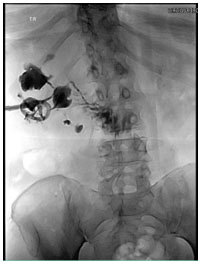

More recently, the patient presented with acute onset fevers and right flank pain. Computed tomography (CT) abdomen and pelvis showed xanthogranulomatous pyelonephritis as well as a perinephric abscess. The patient underwent percutaneous drainage of the abscess and placement of a nephrostomy. The patient underwent antegrade nephrostogram which demonstrated contrast in the small bowel and reno-duodenal fistula (Figure 2 and Figure 3). Initially, the patient was treated conservatively with intravenous antibiotics. Nuclear scan of the kidney showed it to be a non-functional kidney as a result of the infection.

Figure 3: Antegrade nephrostogram showing reno-duodenal fistula.

Share Image: